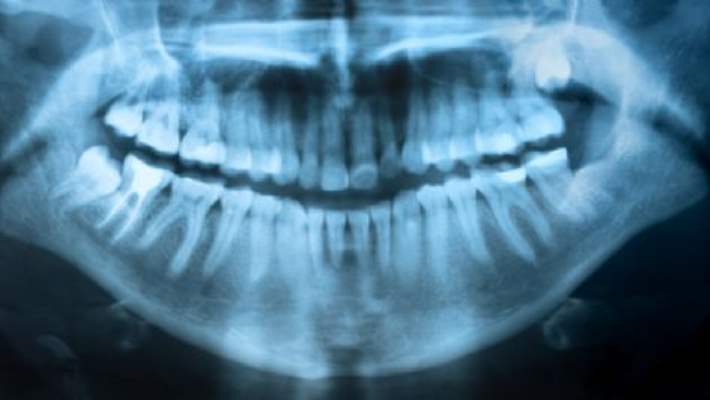

Yirmilik dişin yan çıkması halinde bütün sorunlar bir arada da yaşanabilir. Ağrı yapabilir, öndeki dişi çürütebilir. Öndeki dişleri ittirdiği için öndeki bütün dişlerin çarpık olmasına neden olabilir. Bu gibi durumlarda yirmi yaş dişlerinin çekilmesi gerekir.

Bu dişlerin çekimi normal bir çekim değildir. Bu nedenle mutlaka bu konuda deneyimli bir hekim tarafından yapılmalıdır.